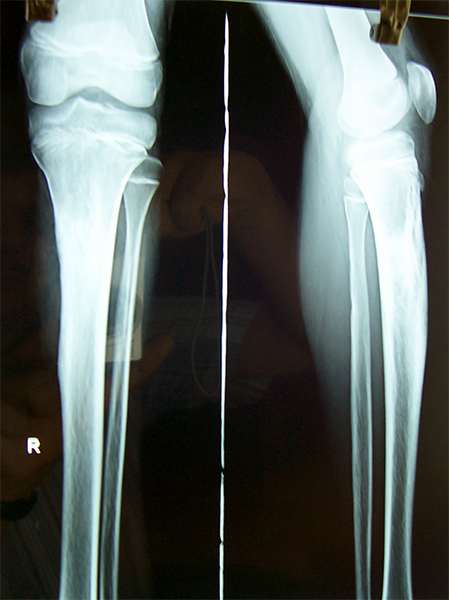

Case:3 Ewings Tibia

Spine Best doctor in satellite|Best Orthopedic Surgeon

Pre-Op

Spine Treatment In Jaipur|Sports Injuries Doctor

Post-Op